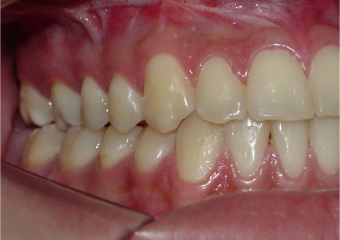

Mordida perfil final